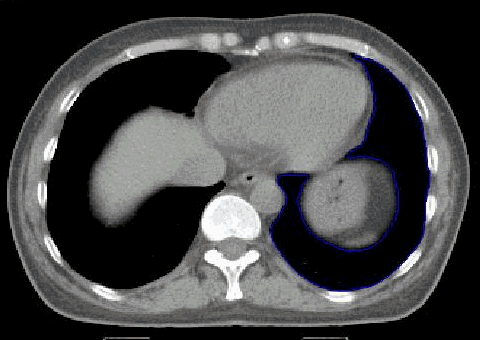

blauer Punkt Inspiration: RIVA von der Thoraxwand distanziert

ohne Inspiration: Herz liegt der Brustwand breitflächig an. Bei Bestrahlung der Brustwand links bekommt der RIVA die volle Dosis ab.